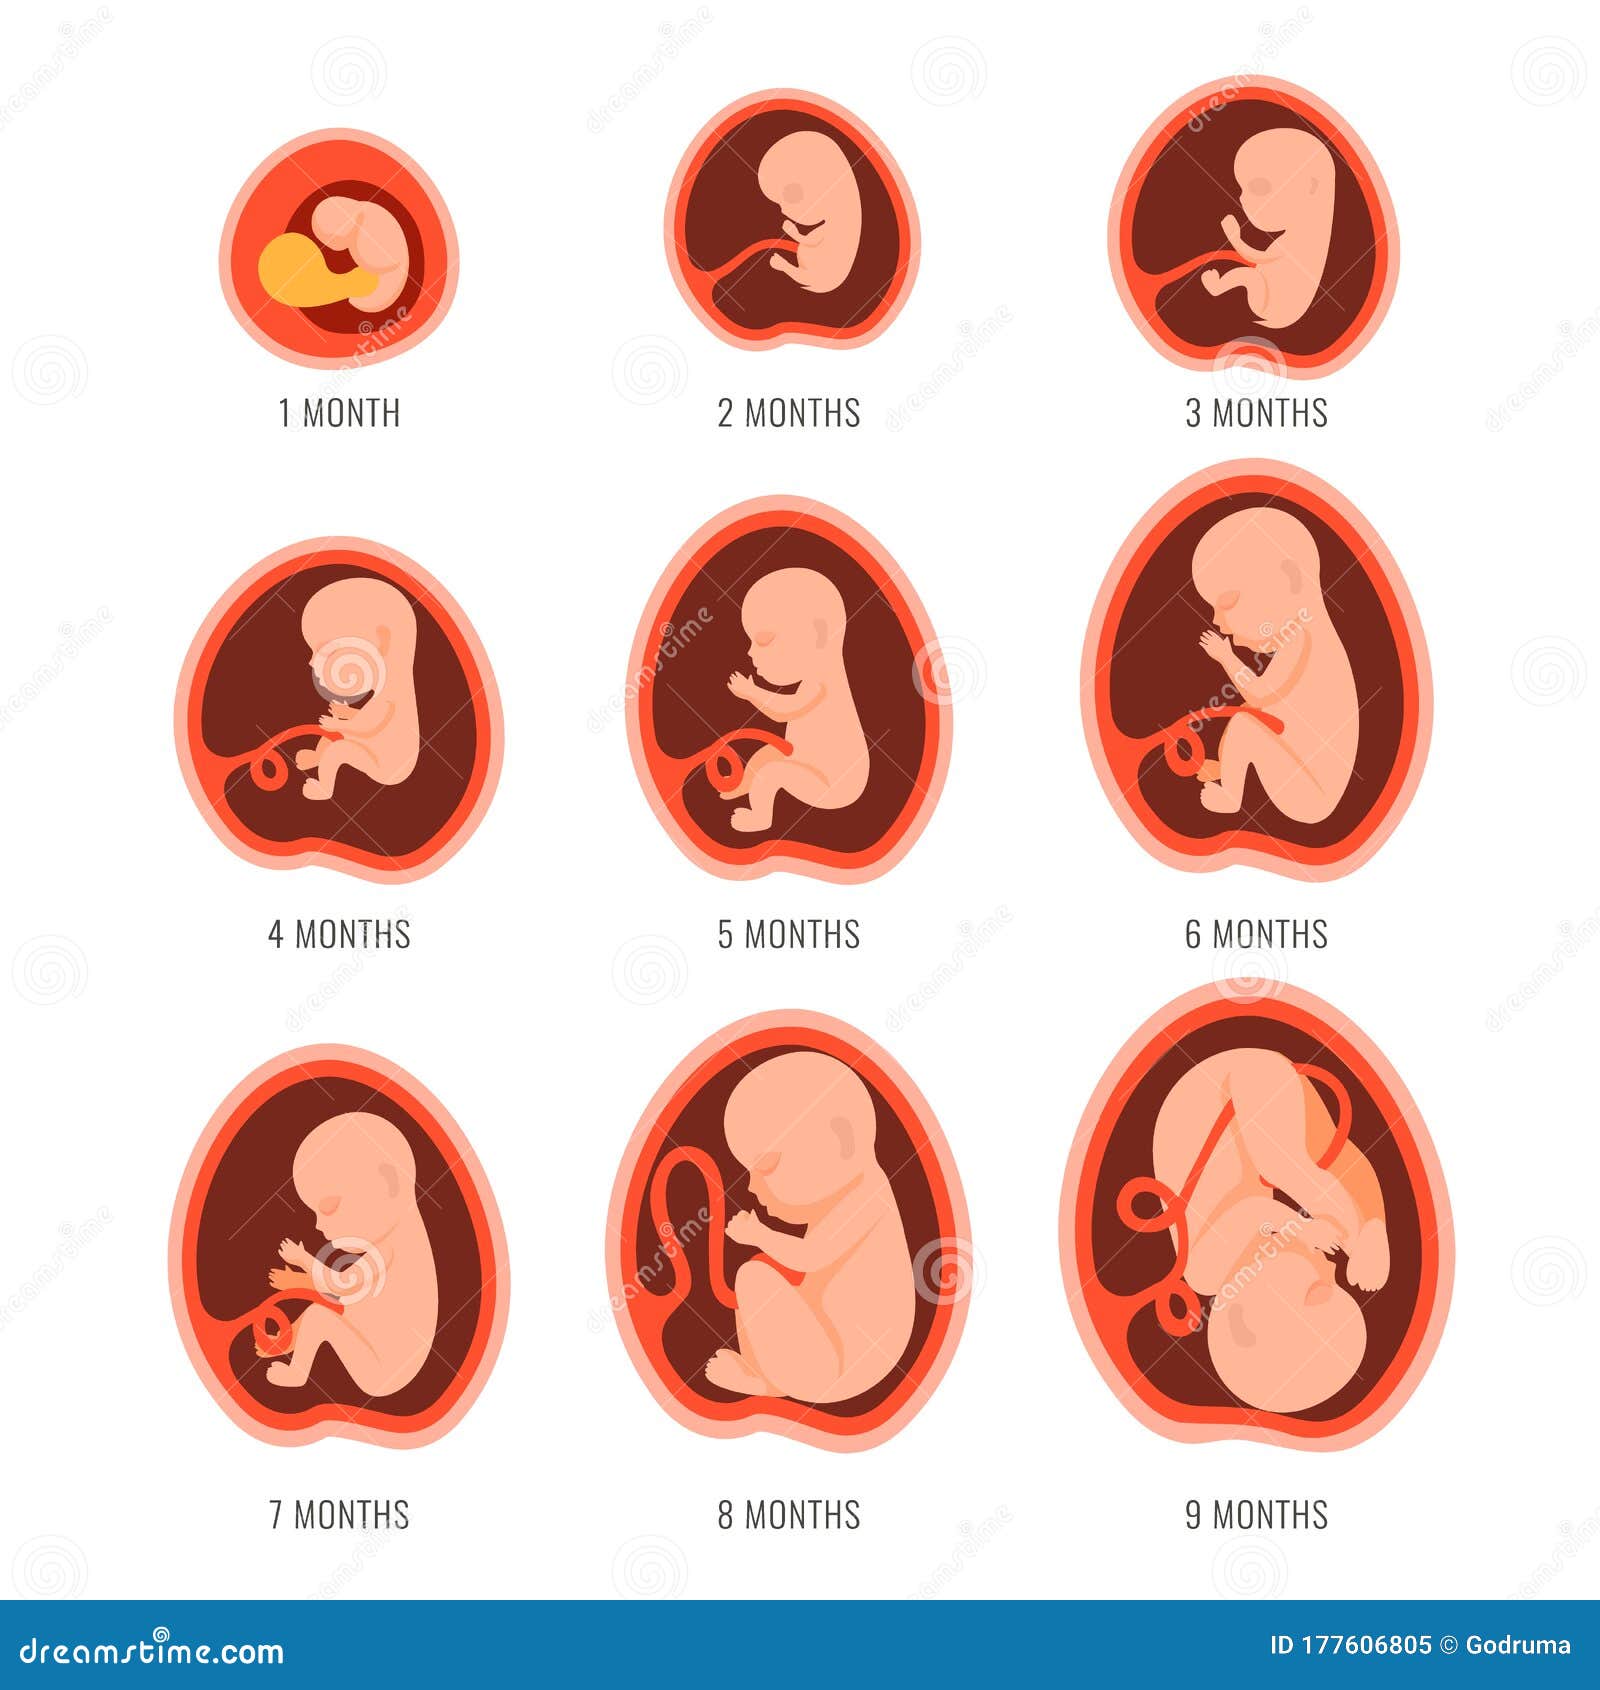

Looking for captivating what does a 2 month old fetus look like images? All, in collaboration with felix.edu.vn, presents a curated selection. Dive into the details for more.

what does a 2 month old fetus look like

We hope you enjoyed this article about what does a 2 month old fetus look like on felix.edu.vn. Let us know what you think in the comments, and discover more related content below.